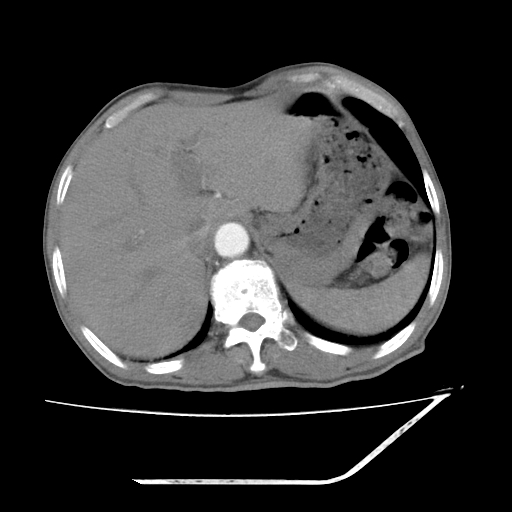

增强

考虑右肾盂癌,肾动脉受侵,右肾功能减退,右肾盂输尿管积水,管壁增厚,考虑种植转移,应该把下面扫完的

支持右侧肾盂癌伴肾静脉瘤栓形成可能性大,右肾结石.肝右叶后段低密度影,不除外转移.

右肾盂旁ca并肾静脉瘤栓形成/肾功能降低。

右肾结石。

支持 右侧肾盂癌伴肾静脉瘤栓形成可能性大,右肾结石;肝右叶后段低密度影,不除外转移。

1.右侧肾盂癌伴肾盂积水。

2.肾脏功能减退,原因有:(1)肾动脉受侵。(2)肾静脉受侵(3)肾积水,等。本例,肾动脉显影较好,但受压明显;肾静脉无明显显示,受压或静脉癌栓,下腔静脉腔内未见明显充盈缺损。

3.右侧上段输尿管扩张,原因:(1)积水所致;(2)种植。